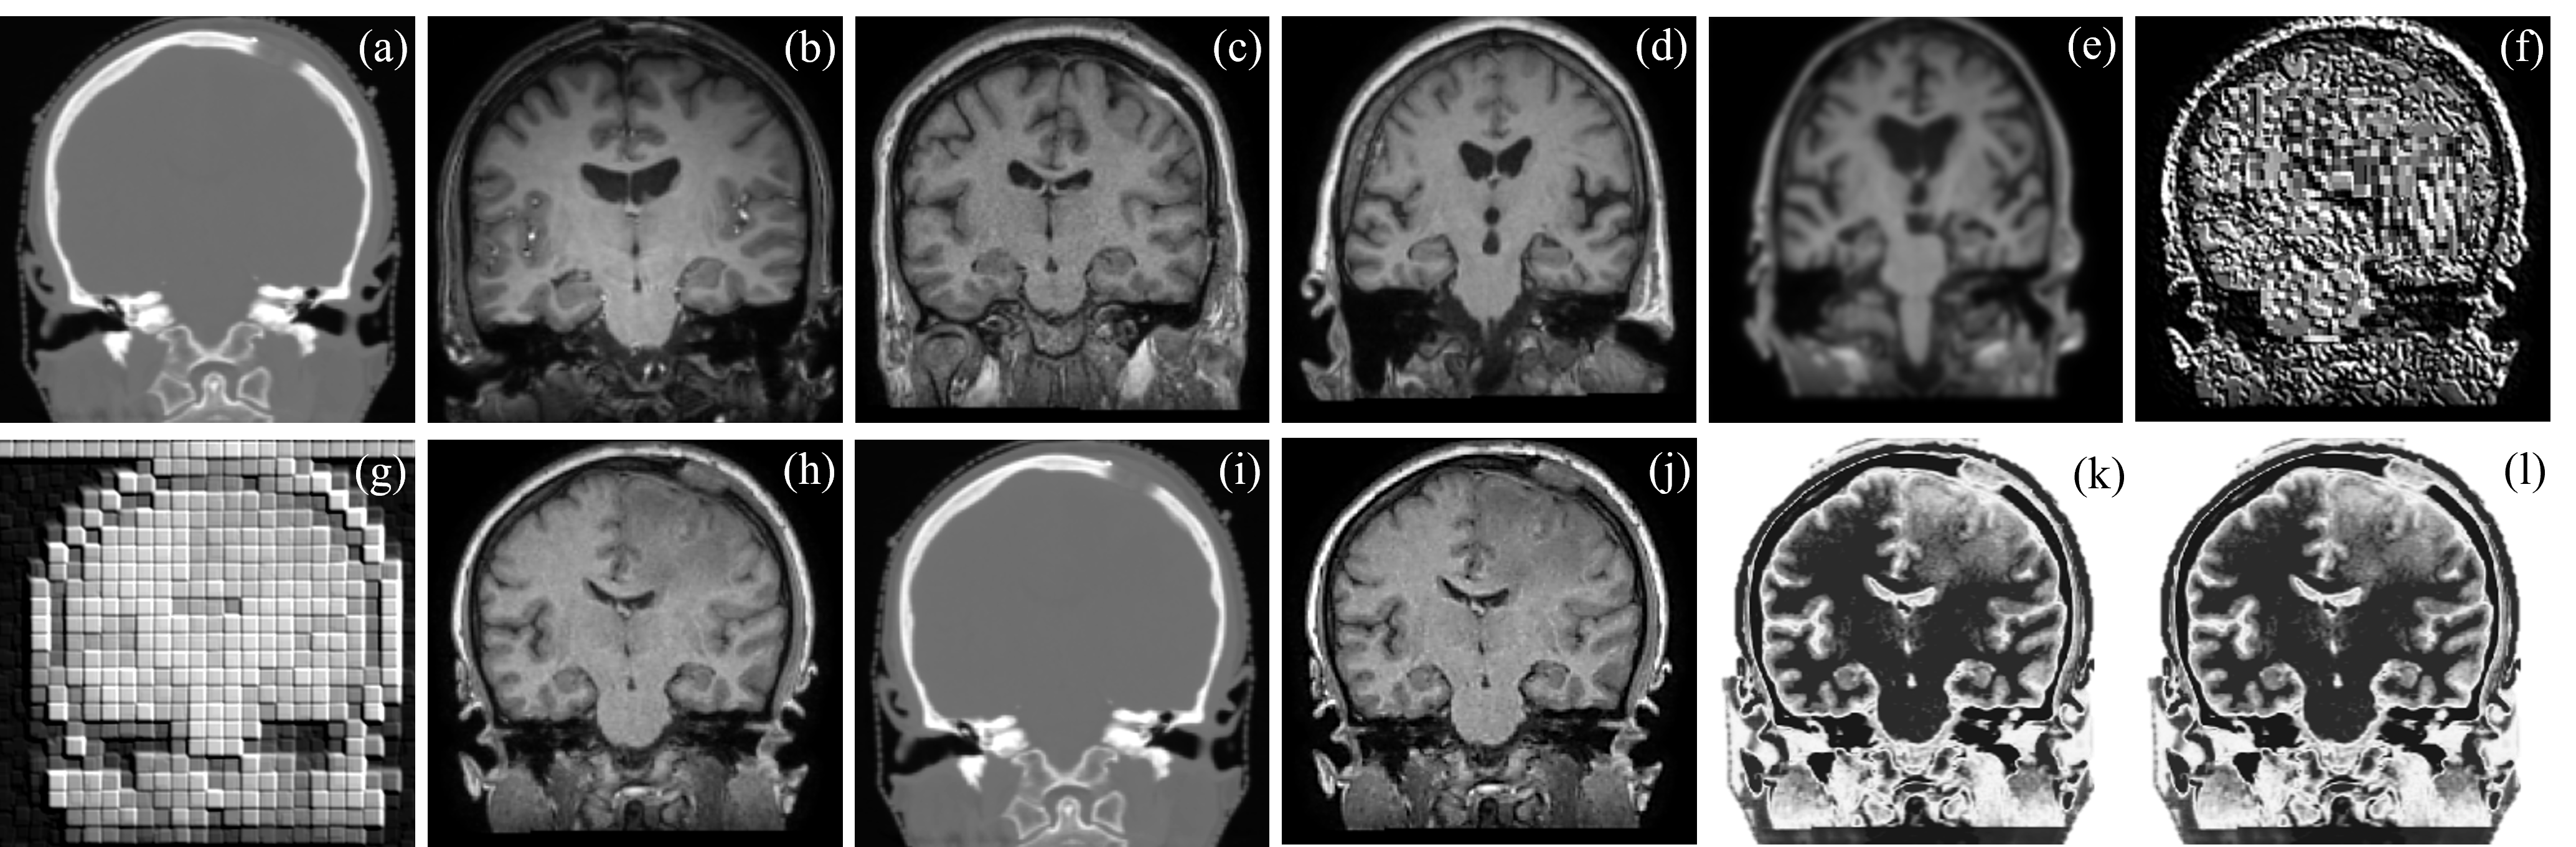

Figure 4: (without ground truth) Qualitative analysis of unpaired image translation of brain CT-MRI-CT ((a) to (j)), and cross-sectional face MRI-CT-MRI ((k) to (t)): (a-b) Unpaired CT-MRI and (k-l) unpaired MRI-CT; translated (c) MRI and (m) CT by 8×8888\times 8; translated (d) MRI and (n) CT by 16×16161616\times 16; translated (e) MRI and (o) CT by 32×32323232\times 32; translated (f) MRI and (p) CT by 64×64646464\times 64; translated (g) MRI and (q) CT by random target modality image; translated (h) MRI and (r) CT by average image of target modality; translated (i) MRI and (s) CT by sample target PDF; and back translated (j) CT from (d) and back translated (t) MRI from (n).

Fig. 3 displays a qualitative result obtained using the pCCGAN by different conditioning scenarios for unpaired cyclic CT-MRI translation. Fig. 3 (j) shows ground truth MRI. One may observe that the MRI generated by conditioning of 16×16161616\times 16 patches (Fig. 3 (h)) optimally utilizes the cross-neighborhood pixel information and achieves superior translation and restoration. Quantitative and ablation test analysis for 100 test image translations are presented in Table I. This confirms the superiority of proposed approach conditioned with 16×16161616\times 16 concatenated alternate patches with DiL. Further, Fig. 4 (a) to (t) display a few qualitative results for unpaired cyclic CT-MRI-CT and MRI-CT-MRI translation when the ground truth is not present. One may observe from Fig. 4 that the proposed approach performs superior unpaired translation even in the absence of ground truth.